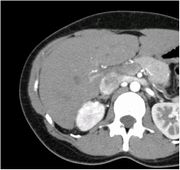

CT画像